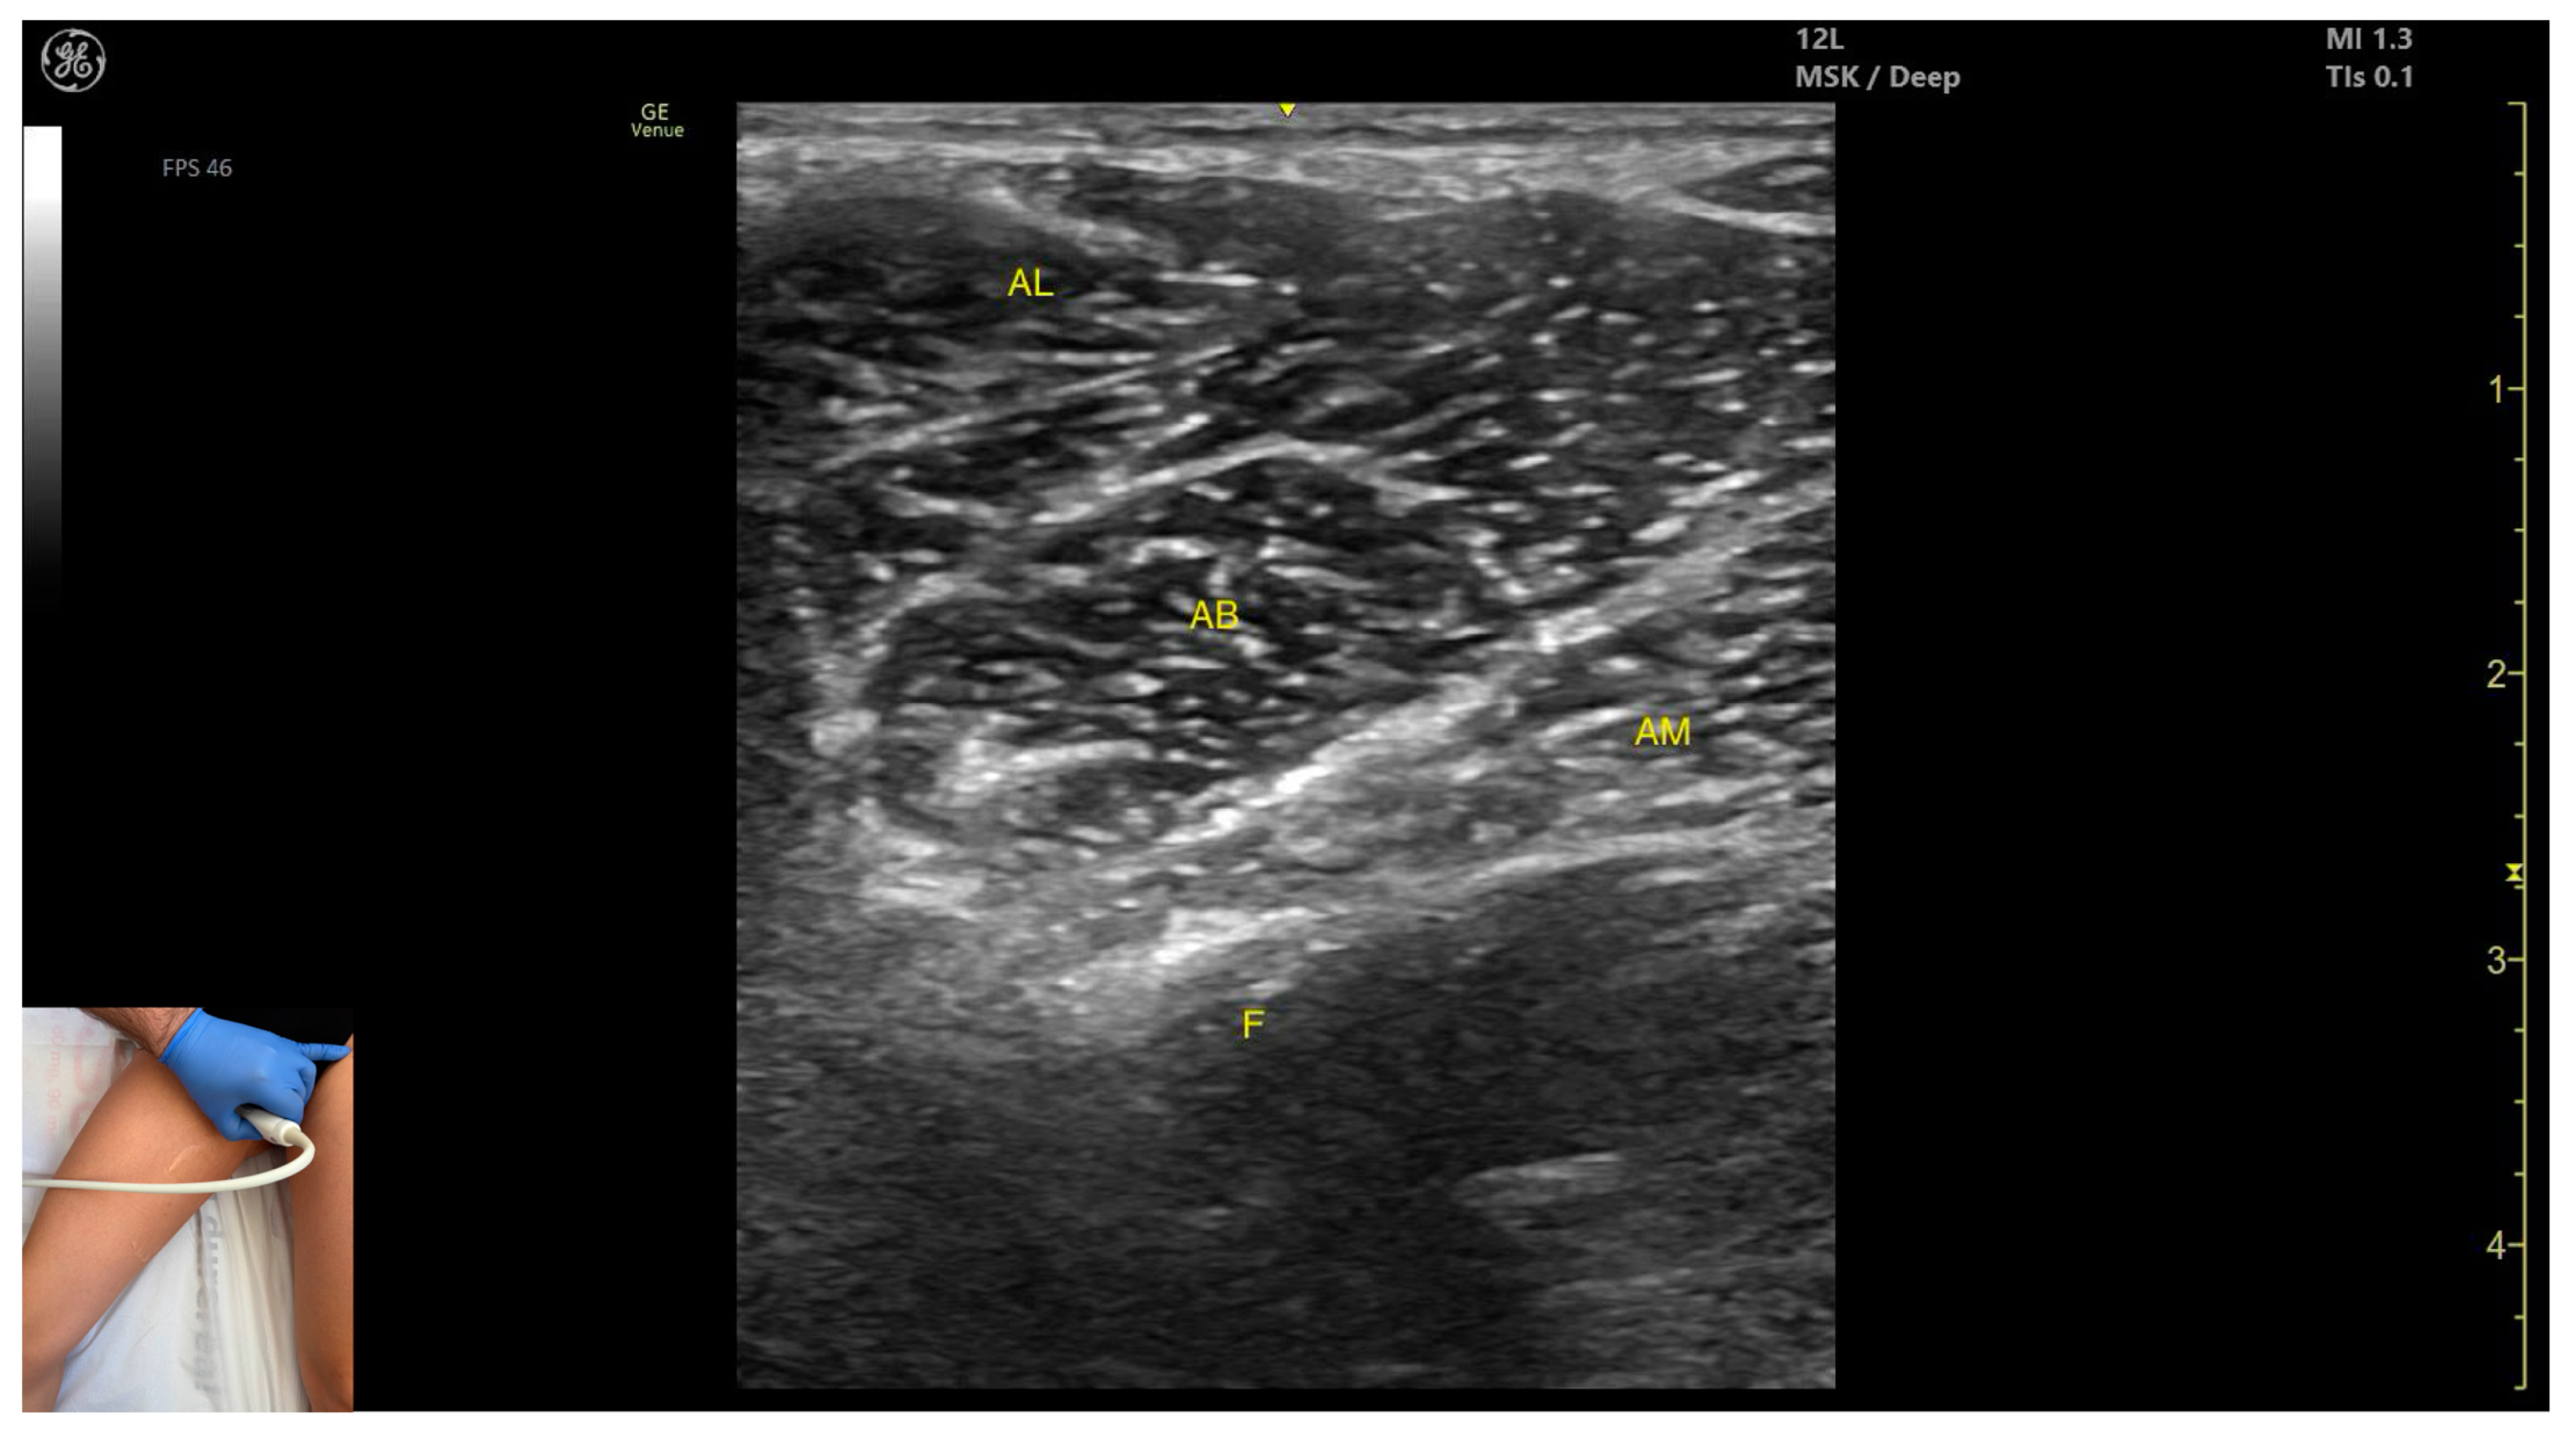

3.7. Adductor Longus (AL)

3.7.2. Ultrasound Identification

3.7.3. Key Ultrasound Landmarks

- Muscle position: It is the most superficial muscle mass at this level. Lateral to it lies the sartorius muscle, and medially, the gracilis muscle. The adductor canal is also visualized laterally.

- External fascia: It presents a pronounced fascia that separates it from the adductor magnus, adductor brevis, sartorius, and gracilis muscles during botulinum toxin injection.

- Dynamic evaluation: During dynamic evaluation, scanning proximally toward the hip joint, the adductor brevis, which lies deep to the adductor longus, becomes more prominent. Scanning distally toward the distal third of the medial thigh, the adductor longus gradually decreases in thickness until it disappears from view, at which point the gracilis and sartorius muscles become adjacent (Video S2). Contraction is visible during hip adduction and internal rotation maneuvers.

3.7.4. Clinical Implications and Injection Strategy

3.8. Adductor Magnus (AM)

3.8.2. Ultrasound Identification

3.8.3. Key Ultrasound Landmarks

- Muscle morphology: It is the largest and deepest muscle of the adductor group.

- Muscle position: It is the first muscle mass superficial to the femoral cortex at this level. It is covered superficially by the gracilis muscle; medial to it lies the semimembranosus.

- External fascia: It has a well-defined fascia separating it from the gracilis and semimembranosus, supporting safe BoNT-A injections.

- Dynamic evaluation: During dynamic evaluation, scanning distally toward the knee joint, a reduction in muscle bulk is observed in both the AM and gracilis. Muscle contraction is visible during hip adduction and hip flexion maneuvers.

3.8.4. Clinical Implications and Injection Strategy

| Adductor Longus | Proximal third of medial thigh | Gracilis (medial), sartorius (lateral), adductor canal (lateral), and adductor brevis (deep) | Transverse scan on upper medial thigh | Confirm muscle position and relations, avoid structures in adductor canal |

| Adductor Magnus | Proximal third of medial thigh | Gracilis (superficial) and semimembranosus (medial) | Transverse scan with the hip abducted, externally rotated, and semi-flexed and the knee in semi-flexion | Identify deep muscle mass below gracilis |